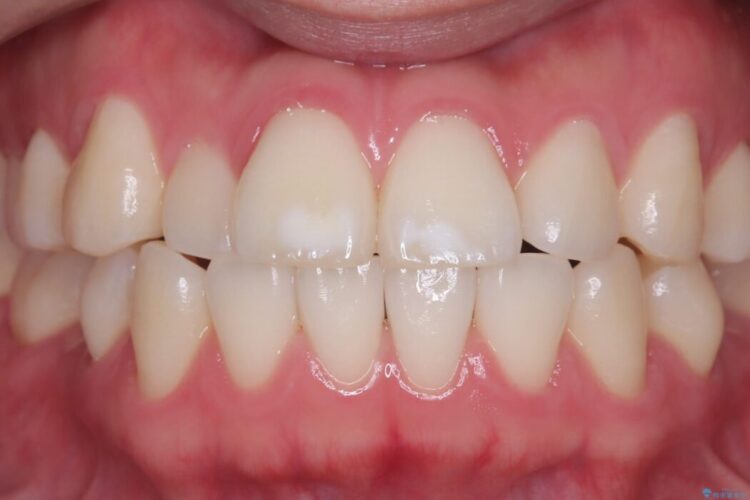

長期的な安定性を重視したセラミック治療

歯と歯の間に虫歯があった患者様です。